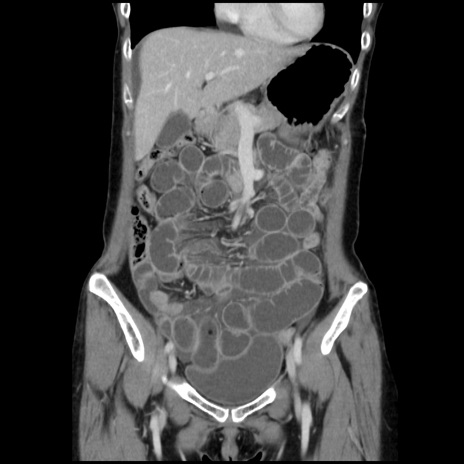

症例32(冠状断像)

【症例】40歳代 女性

【主訴】上腹部痛、嘔気・嘔吐

【現病歴】約9時間前頃から急に上腹部痛、嘔気、嘔吐が出現。改善しないため救急要請。

【既往歴】子宮頚癌(広汎子宮全摘術、放射線療法)、腸閉塞

【身体所見】腹部:平坦、軟、腸雑音亢進、上腹部を中心に腹部全体に圧痛あり。

【データ】WBC 8400、CRP 0.03